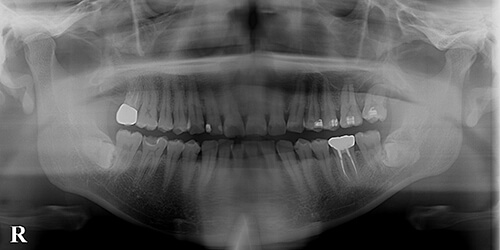

【治療後】

無事矯正的挺出が完了しました。期間として約半年。歯の移植術や抜歯再植術に比べてこの方法が優れているのは、8(親知らず)を生活歯として活用できることです。最後方臼歯には一番力が掛かるので、出来れば生活歯として使って行きたいものです。

- 【治療期間】約6か月

- 【治療費】約25万円

- 【一般的なリスクや副作用】長らく埋もれていた親知らずは、骨性の癒着を起こしている可能性があり、挺出できないこともあります。

抜歯後のインプラントが難しい症例でしたが、本来不要である親知らずが有効活用できました。